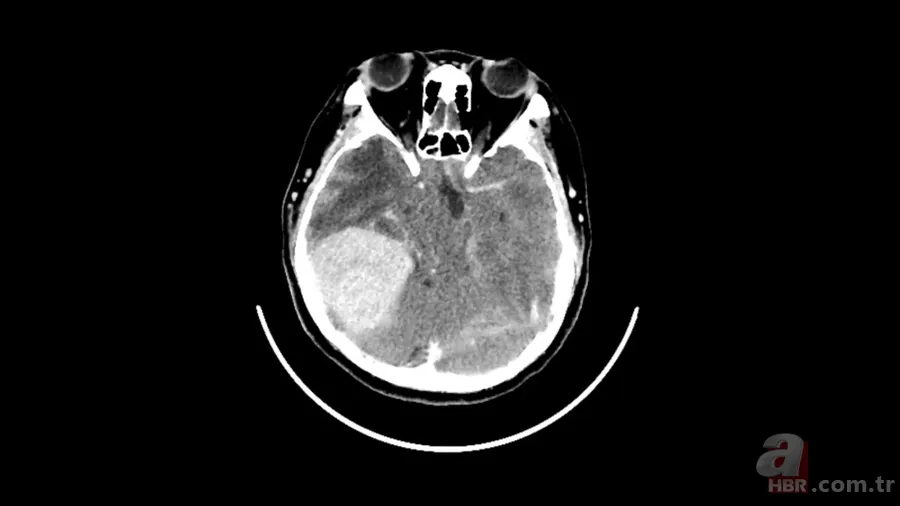

Yapılan beyin taraması tıp ekibini şaşkına çevirdi. Görüntülerde kadının beyninde menenjiyom adı verilen oldukça büyük bir tümör bulunduğu ortaya çıktı. Daha da dikkat çekici olan ise kadının bu büyüklükteki bir kitleye rağmen şiddetli baş ağrısı, görme kaybı veya nörolojik bozukluk gibi tipik belirtiler göstermemiş olmasıydı.